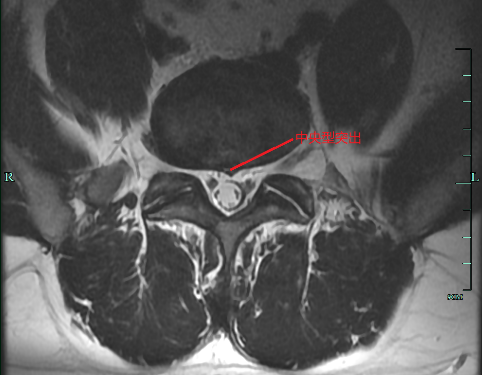

①中央型突出(少见)

女性,48 岁, L4/5 椎间盘突出,中央型